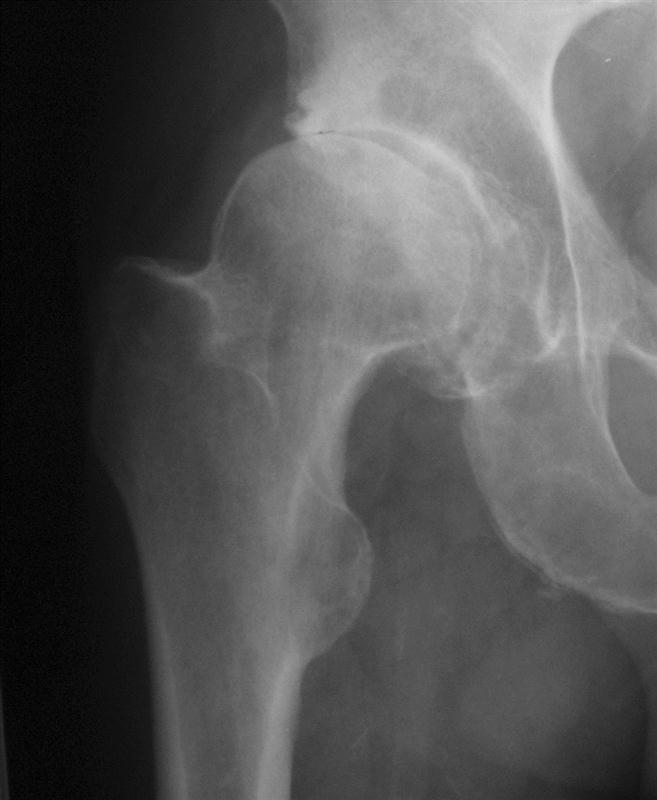

Hüftprothese (künstliches Hüftgelenk)

In den letzten Jahren haben sich an der Hüfte minimalinvasive Eingriffe an der Hüfte bei beginnenden Arthrosen bewährt. Dabei werden über einen kleinen Zugang von ventral die Randanbauten am Schenkelhals und Pfanne abgetragen.

Bei der Hüftendoprothetik haben wir uns für bewährte Prothesen mit sehr guten langjährigen Ergebnissen entschieden. Diese werden weichteilschonend implantiert und die Patienten frühmobilisiert. Wichtig ist bei dem operativen Eingriff auch die geringe Komplikationsrate und die gute Plazierbarkeit der Prothese. Die Gleitpaarung besteht aus einem gehärteten Polyäthylen mit kaum noch Abriebpartikeln. Dabei verwenden wir möglichst große Hüftköpfe um ein natürliches Bewegungsgefühl zu erzeugen.

Die Röntgenbilder wurden durch uns angefertigt und fotografiert.